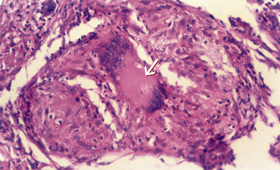

A Mantoux test was non-reactive. The serum level of angiotensin-converting enzyme was 76.2 U/L (normal range, 8–52 U/L). A skin biopsy taken from the palmar rash revealed non-caseating granulomas with multinucleated giant cells (Box 1). No acid-fast bacilli or fungal hyphae were detected on direct staining or subsequent culture of sputum and skin biopsy specimens. The histological features were thus suggestive of sarcoidosis.